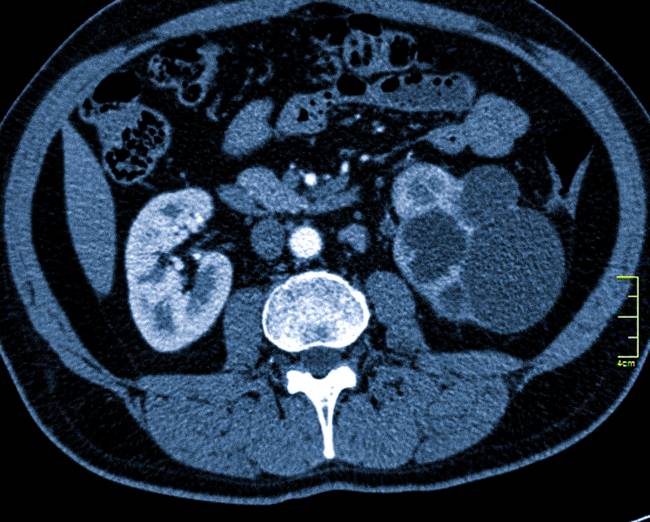

Палочка Коха, вызывающая туберкулез, может быть обнаружена в разных мягкотканных органах (печени, почках, мозге и др.) и костных структурах. Только при комплексной диагностике проводят дифференциацию патологии от других заболеваний, определяют степень, локализацию и тяжесть патологического процесса.

image Туберкулез почки

Патология развивается на фоне деятельности палочки Коха. После попадания в организм она поражает не только органы дыхания, но и другие важные системы, в т.ч. печень, почки, мозг и костную ткань. Денситометрия и томография при туберкулезе – это лучшие способы определения локализации бактерий и подбора оптимального способа лечения.